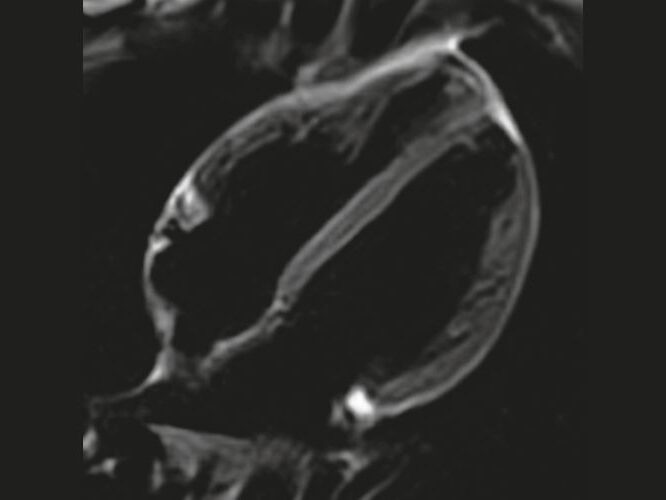

Cardiac imaging with 3T MRI offers detailed heart structure visualization and function for accurate detection of cardiovascular pathologies.